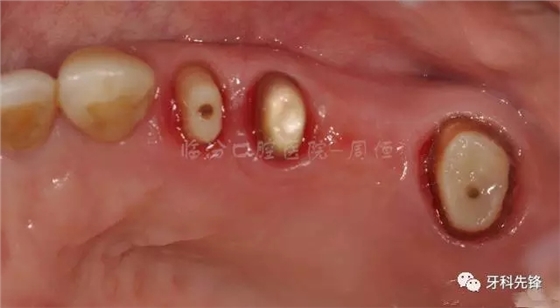

圖9去除腐質(zhì)口內(nèi)照

圖10冠延長(zhǎng)術(shù)后照

圖11術(shù)后一個(gè)月纖維樁修復(fù) 牙體預(yù)備